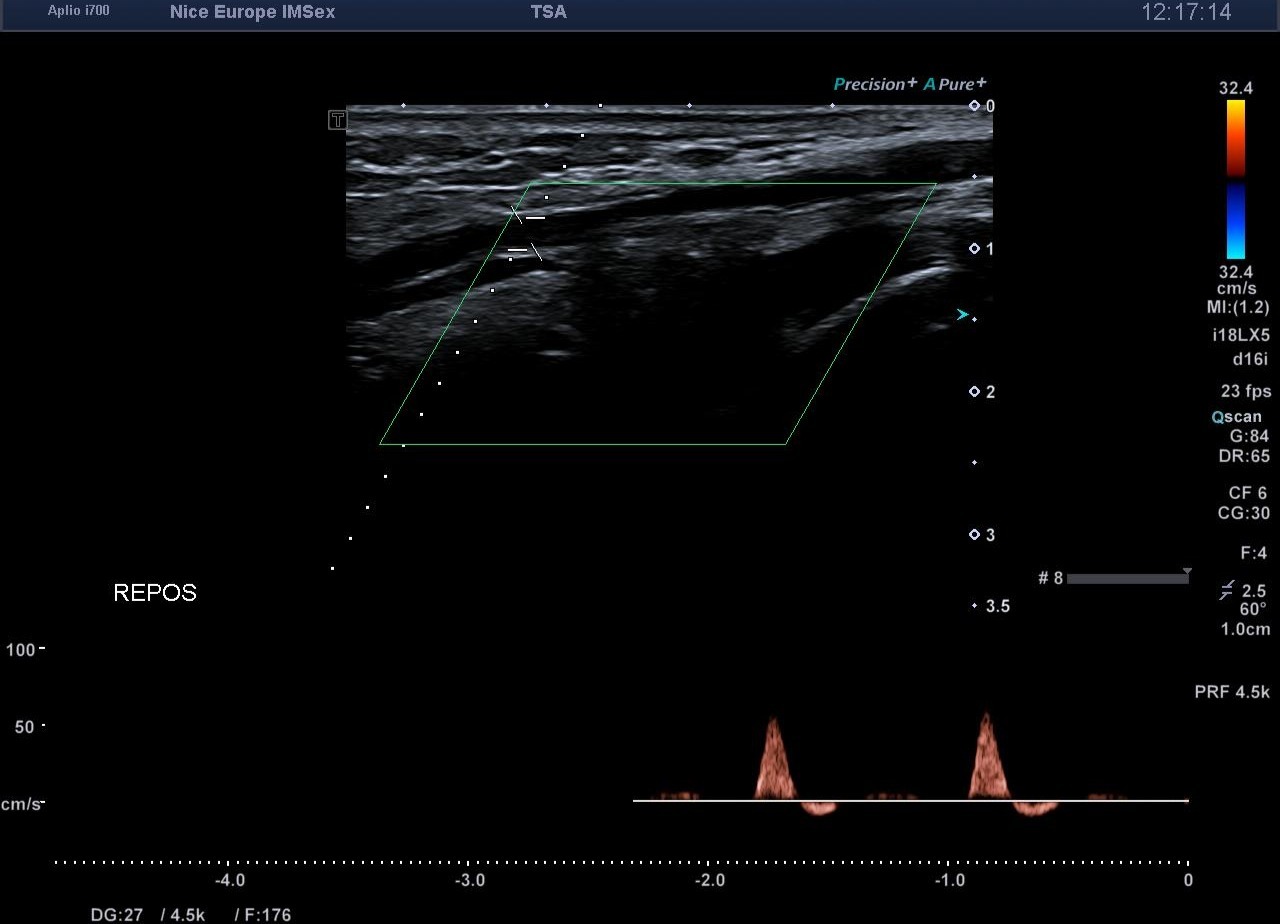

Devant ce morphotype athlétique et la négativité de l'examen statique, un test de provocation par échographie dynamique est entrepris pour rechercher un syndrome de l'artère poplitée piégée (ou piège poplité). Lors d’une manœuvre de flexion plantaire contrariée (mise en tension soutenue des muscles de la loge postérieure contre résistance), on objective en temps réel :

1. 1. Une compression extrinsèque majeure de l’artère poplitée par les chefs musculaires gastrocnémiens.

2. 2. Une occlusion artérielle complète (diastolique et systolique) au point de compression.

3. 3. Une abolition du flux artériel distal.

Pour confirmer de manière spécifique que l'occlusion siège bien au niveau du creux poplité, l'échographiste doit interroger l'artère tibiale antérieure (ATA). Cheminant dans la loge antérieure de la jambe, l'ATA est soustraite à l'hyperpression de la loge postérieure. Si le flux de l'ATA s'effondre lors de la flexion plantaire contrariée, cela atteste formellement que l'obstacle artériel se situe en amont, signant ainsi le piège poplité

• Spécificité du retentissement distal : L'arrêt du flux sur l'artère tibiale antérieure (ATA) lors des manœuvres de provocation est le témoin fiable et spécifique d'une occlusion poplitée extrinsèque.